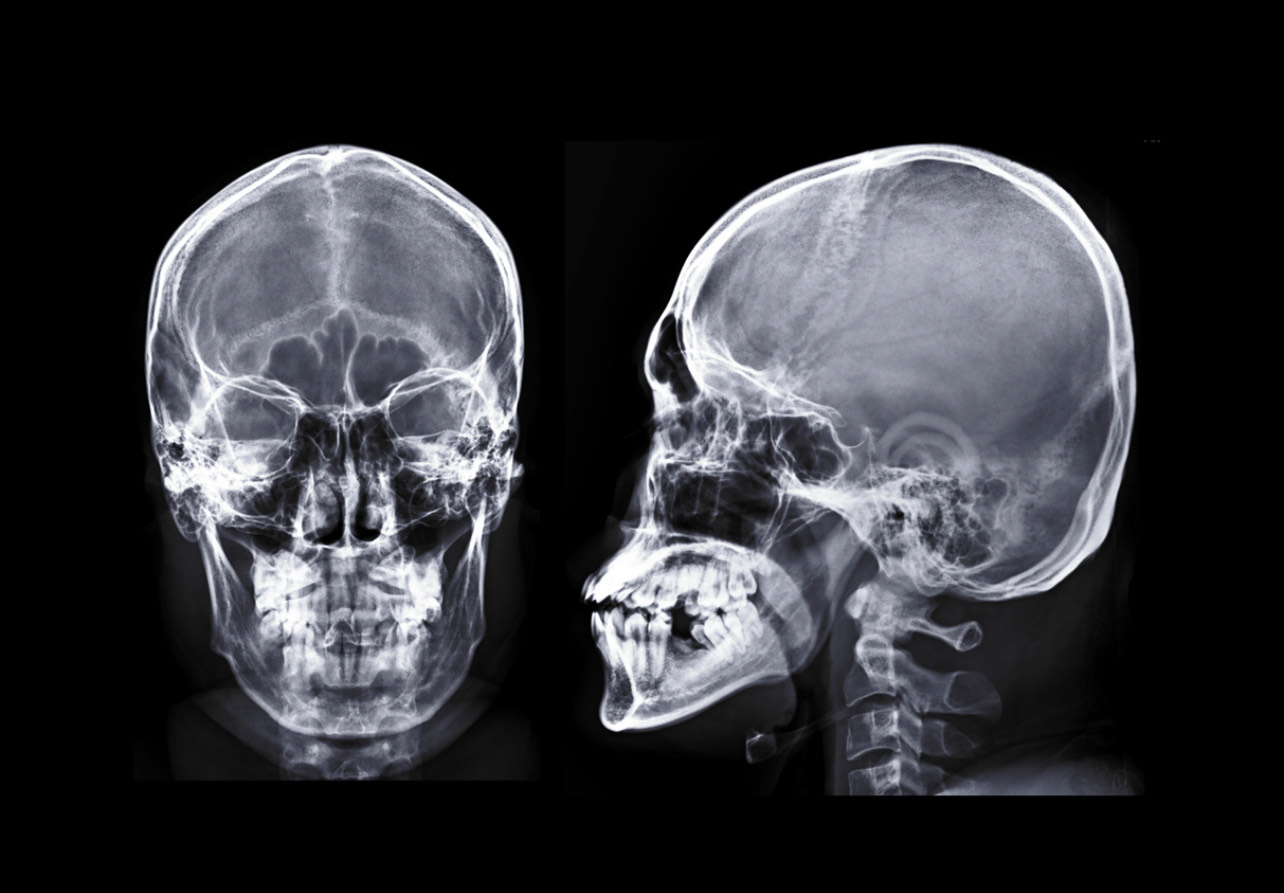

Anatomia twarzy

Ta lekcja pokazuje budowę twarzy w kontekście pracy kosmetologa. Zrozumienie układu tkanek, mięśni i struktur anatomicznych pozwala wykonywać zabiegi świadomie, bezpiecznie i z większą precyzją, co bezpośrednio przekłada się na efekty oraz komfort klienta.

- strefy bardziej i mniej bezpieczne w pracy zabiegowej

- miejsca szczególnej ostrożności przy technikach manualnych i aparaturowych